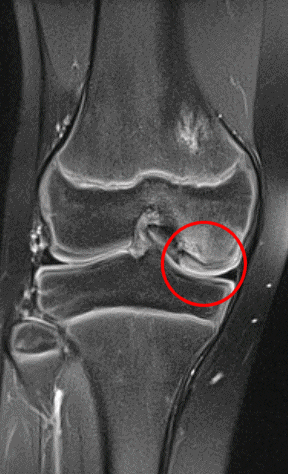

En broskbit med underliggande ben lossnar från metafys. Vanligast i mediala femurkondylen i ålder 10-19 år men kan hända i de flesta leder och även hos vuxna. [1, 2]

Osteokondrit i mediala femurkondylen hos 10-åring

Röntgen, helst DT. Vid låsningar bör MR eller artroskopi utföras [1].